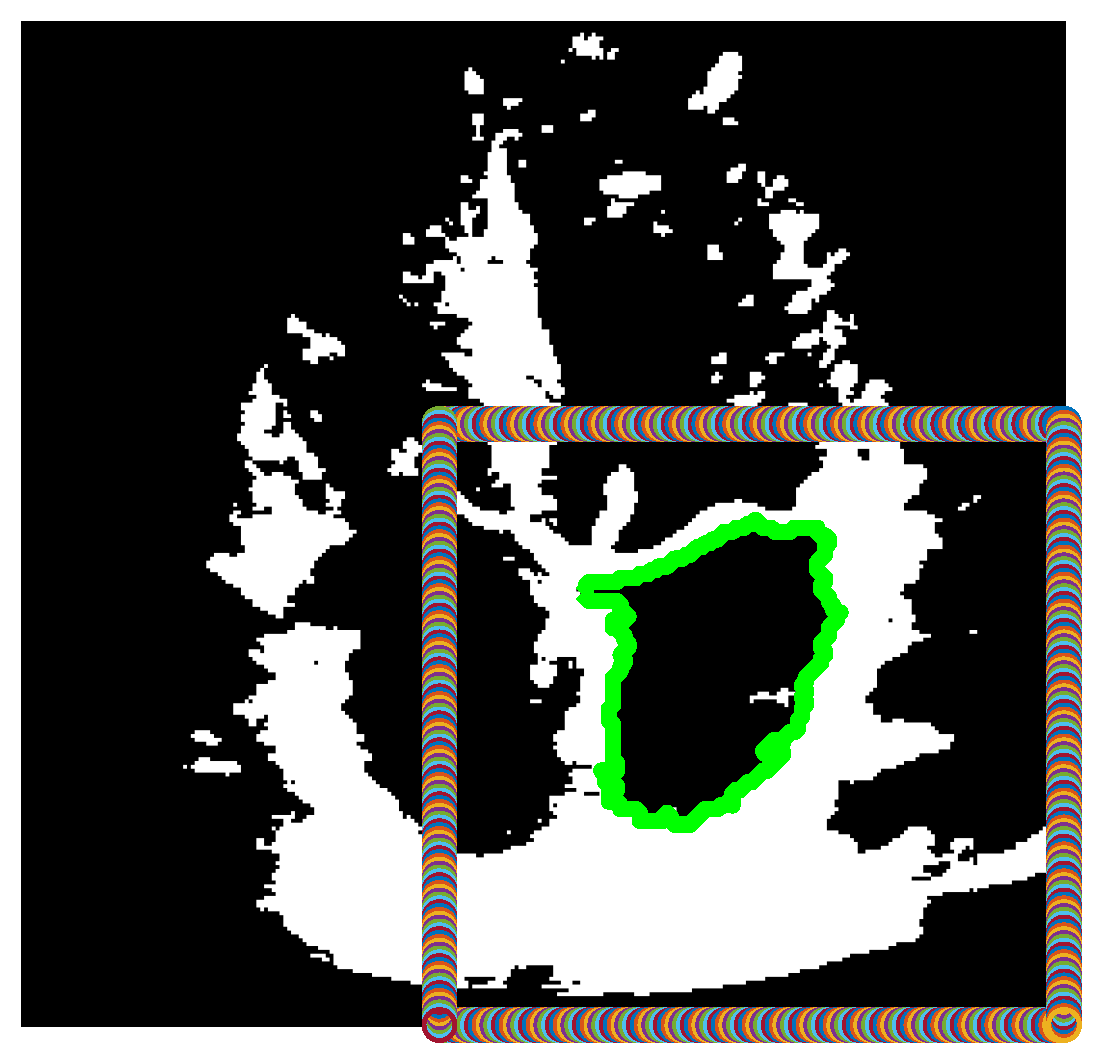

Figure 2 depicts the given algorithm finding the correct closed boundary around the left atrium, which is within the automatically generated box in the bottom right corner, where the left atrium always resides.

Figure 2. Binarized version of the combined frame, after finding a large contour (green) within the box defined in the bottom right corner of the image.